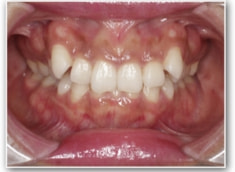

叢生+左下1番先天欠如ケース

治療法:裏側の矯正(リンガルブラケット:舌側矯正)

治療後